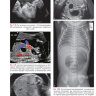

Дефекты передней брюшной стенки